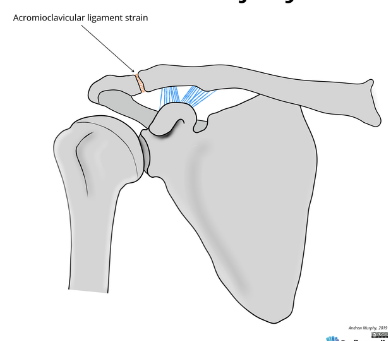

Based off Rockwood classification of acromioclavicular joint injury, what grade would this be?

1